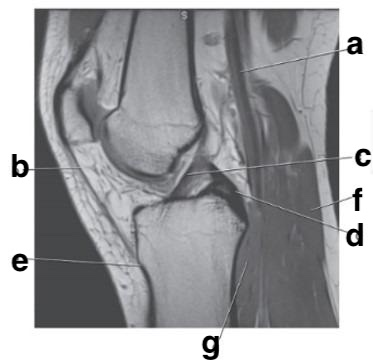

Supraspinatus tendon

e

Achilles tendon

b

c